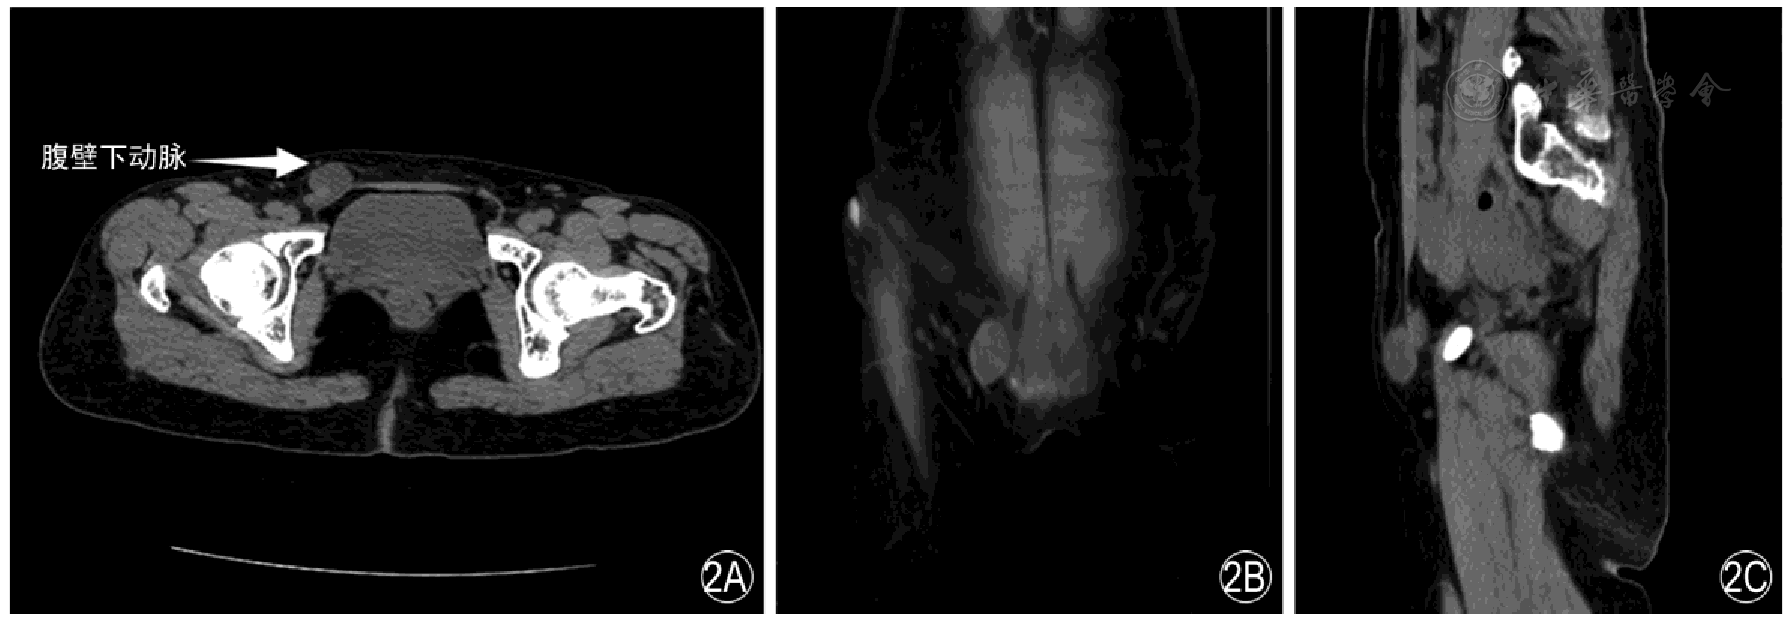

The sensitivity and specificity of MSCT in diagnosing inguinal hernias were 97.79% and 80.00%, respectively, with a kappa value of 0.652. The sensitivity and specificity of high-frequency ultrasound in diagnosing inguinal hernias were 96.32% and 80.00%, respectively, with a kappa value of 0.551. For the diagnosis of indirect hernias, MSCT had a sensitivity of 97.00% and a specificity of 94.44%, with a kappa value of 0.906; for the diagnosis of direct hernias, MSCT had a sensitivity of 94.44% and a specificity of 97.00%, with a kappa value of 0.906. High-frequency ultrasound had a sensitivity of 92.00% and a specificity of 88.89% for diagnosing indirect hernias, with a kappa value of 0.781, and a sensitivity of 88.89% and a specificity of 92.00% for diagnosing direct hernias, with a kappa value of 0.781. Indirect inguinal hernias presented with mixed density or were cystic-solid, all distributed on the anterior side of the inguinal ligament and lateral to the inferior epigastric artery, without a crescent sign or filling of the femoral triangle. Direct hernias were all distributed on the anterior side of the inguinal ligament and medial to the inferior epigastric artery, without filling of the femoral triangle, and often with a lateral crescent sign. The indirect hernia sac was located lateral to the origin of the inferior epigastric artery, and the diameter and shape of the hernia ring varied greatly. The direct hernia sac was located medial to the inferior epigastric artery, with no significant changes in the local abdominal wall, clear intestinal wall layers, no obvious hernia sac neck, and a small amount of fluid dark area could be detected in the hernia sac cavity of some patients. The hernia ring was located medial to the inferior epigastric vessels, and there was a small amount of color blood flow signal in the intestinal wall. The proportions of contents in indirect hernias were, in descending order: intestinal canal, greater omentum, ovary, effusion, intra-abdominal fat, and bladder. The proportions of contents in direct hernias were, in descending order: intestinal canal, intra-abdominal fat, greater omentum, effusion, ovary, fat, and bladder. After Bonferroni correction (corrected significance level of P<0.0083), there were no statistically significant differences in the detection rates of all contents between the two groups (all P>0.0083).